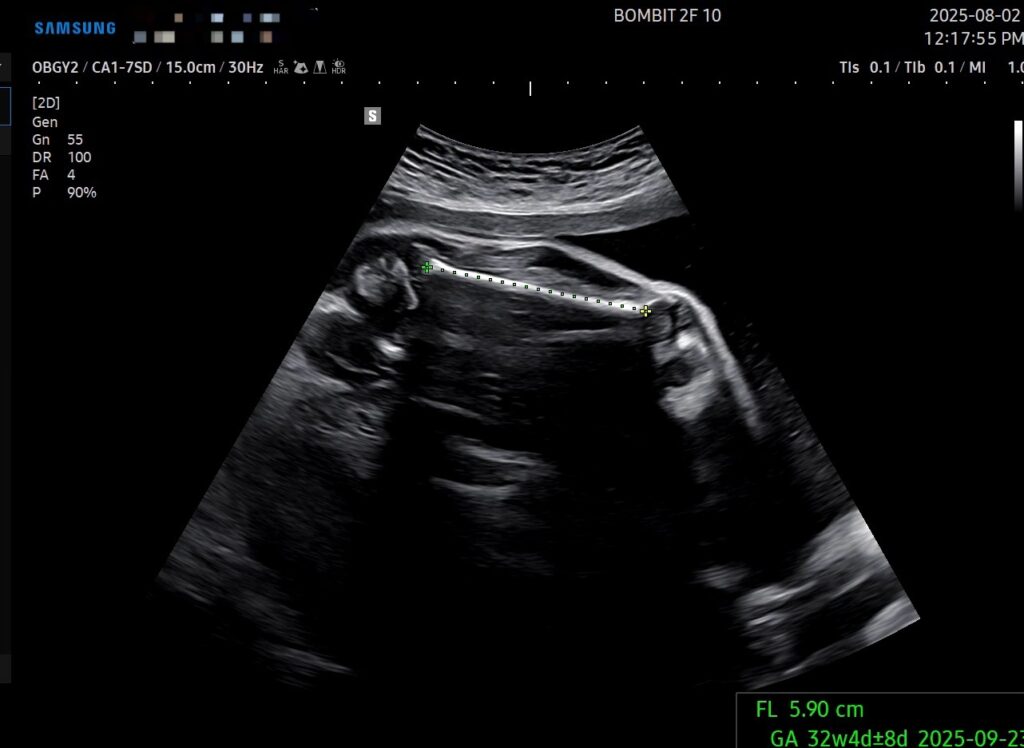

29주 6일차의 초음파인데, 몸무게, 배 둘레, 다리 길이 기준으로 주수는 약 32주로 나온다.

전반적으로 뼈대가 크면서 배도 나온(=살도 잘 붙은) 그런 아기인 듯.

예상 몸무게는 1.958kg인데, 마미톡 주별정보의 30주차 적정 아기 무게는 1.4kg이라고 나온다. 아무리 초음파 측정이 오차범위가 있다지만 단비가 과도하게 큰 건 맞는 듯 하다 ㅜㅜ

- 두상이랑 다리길이는 이 친구 스타일이다. 즉 골격 자체는 원래 이 친구가 큰 아이라서 그런 것이다.